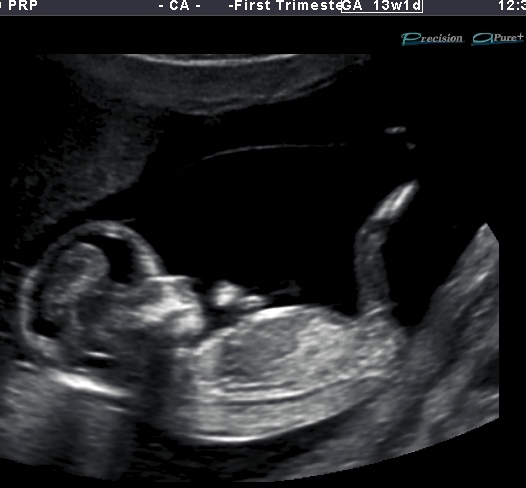

Elico's 13 week 1 day u/s pic

Hi there. I had my NT scan today and wow that bubba was hypo. The sonographer was struggling to get the correct info that was required of her. I was watching the scan closely and i saw nubs every so often and it was on an angle upward but not extremely vertical .... The pics i have of bub are just a handful of cute pics my lovely scanner put on a disk because hubby couldn't attend. i will get the whole lot of pics on monday where hopefully there will be more nub pics. So this is my only pic and im not even sure its a nub unless its a see through the leg one lol. Any advice appreciated.Attachment 12418